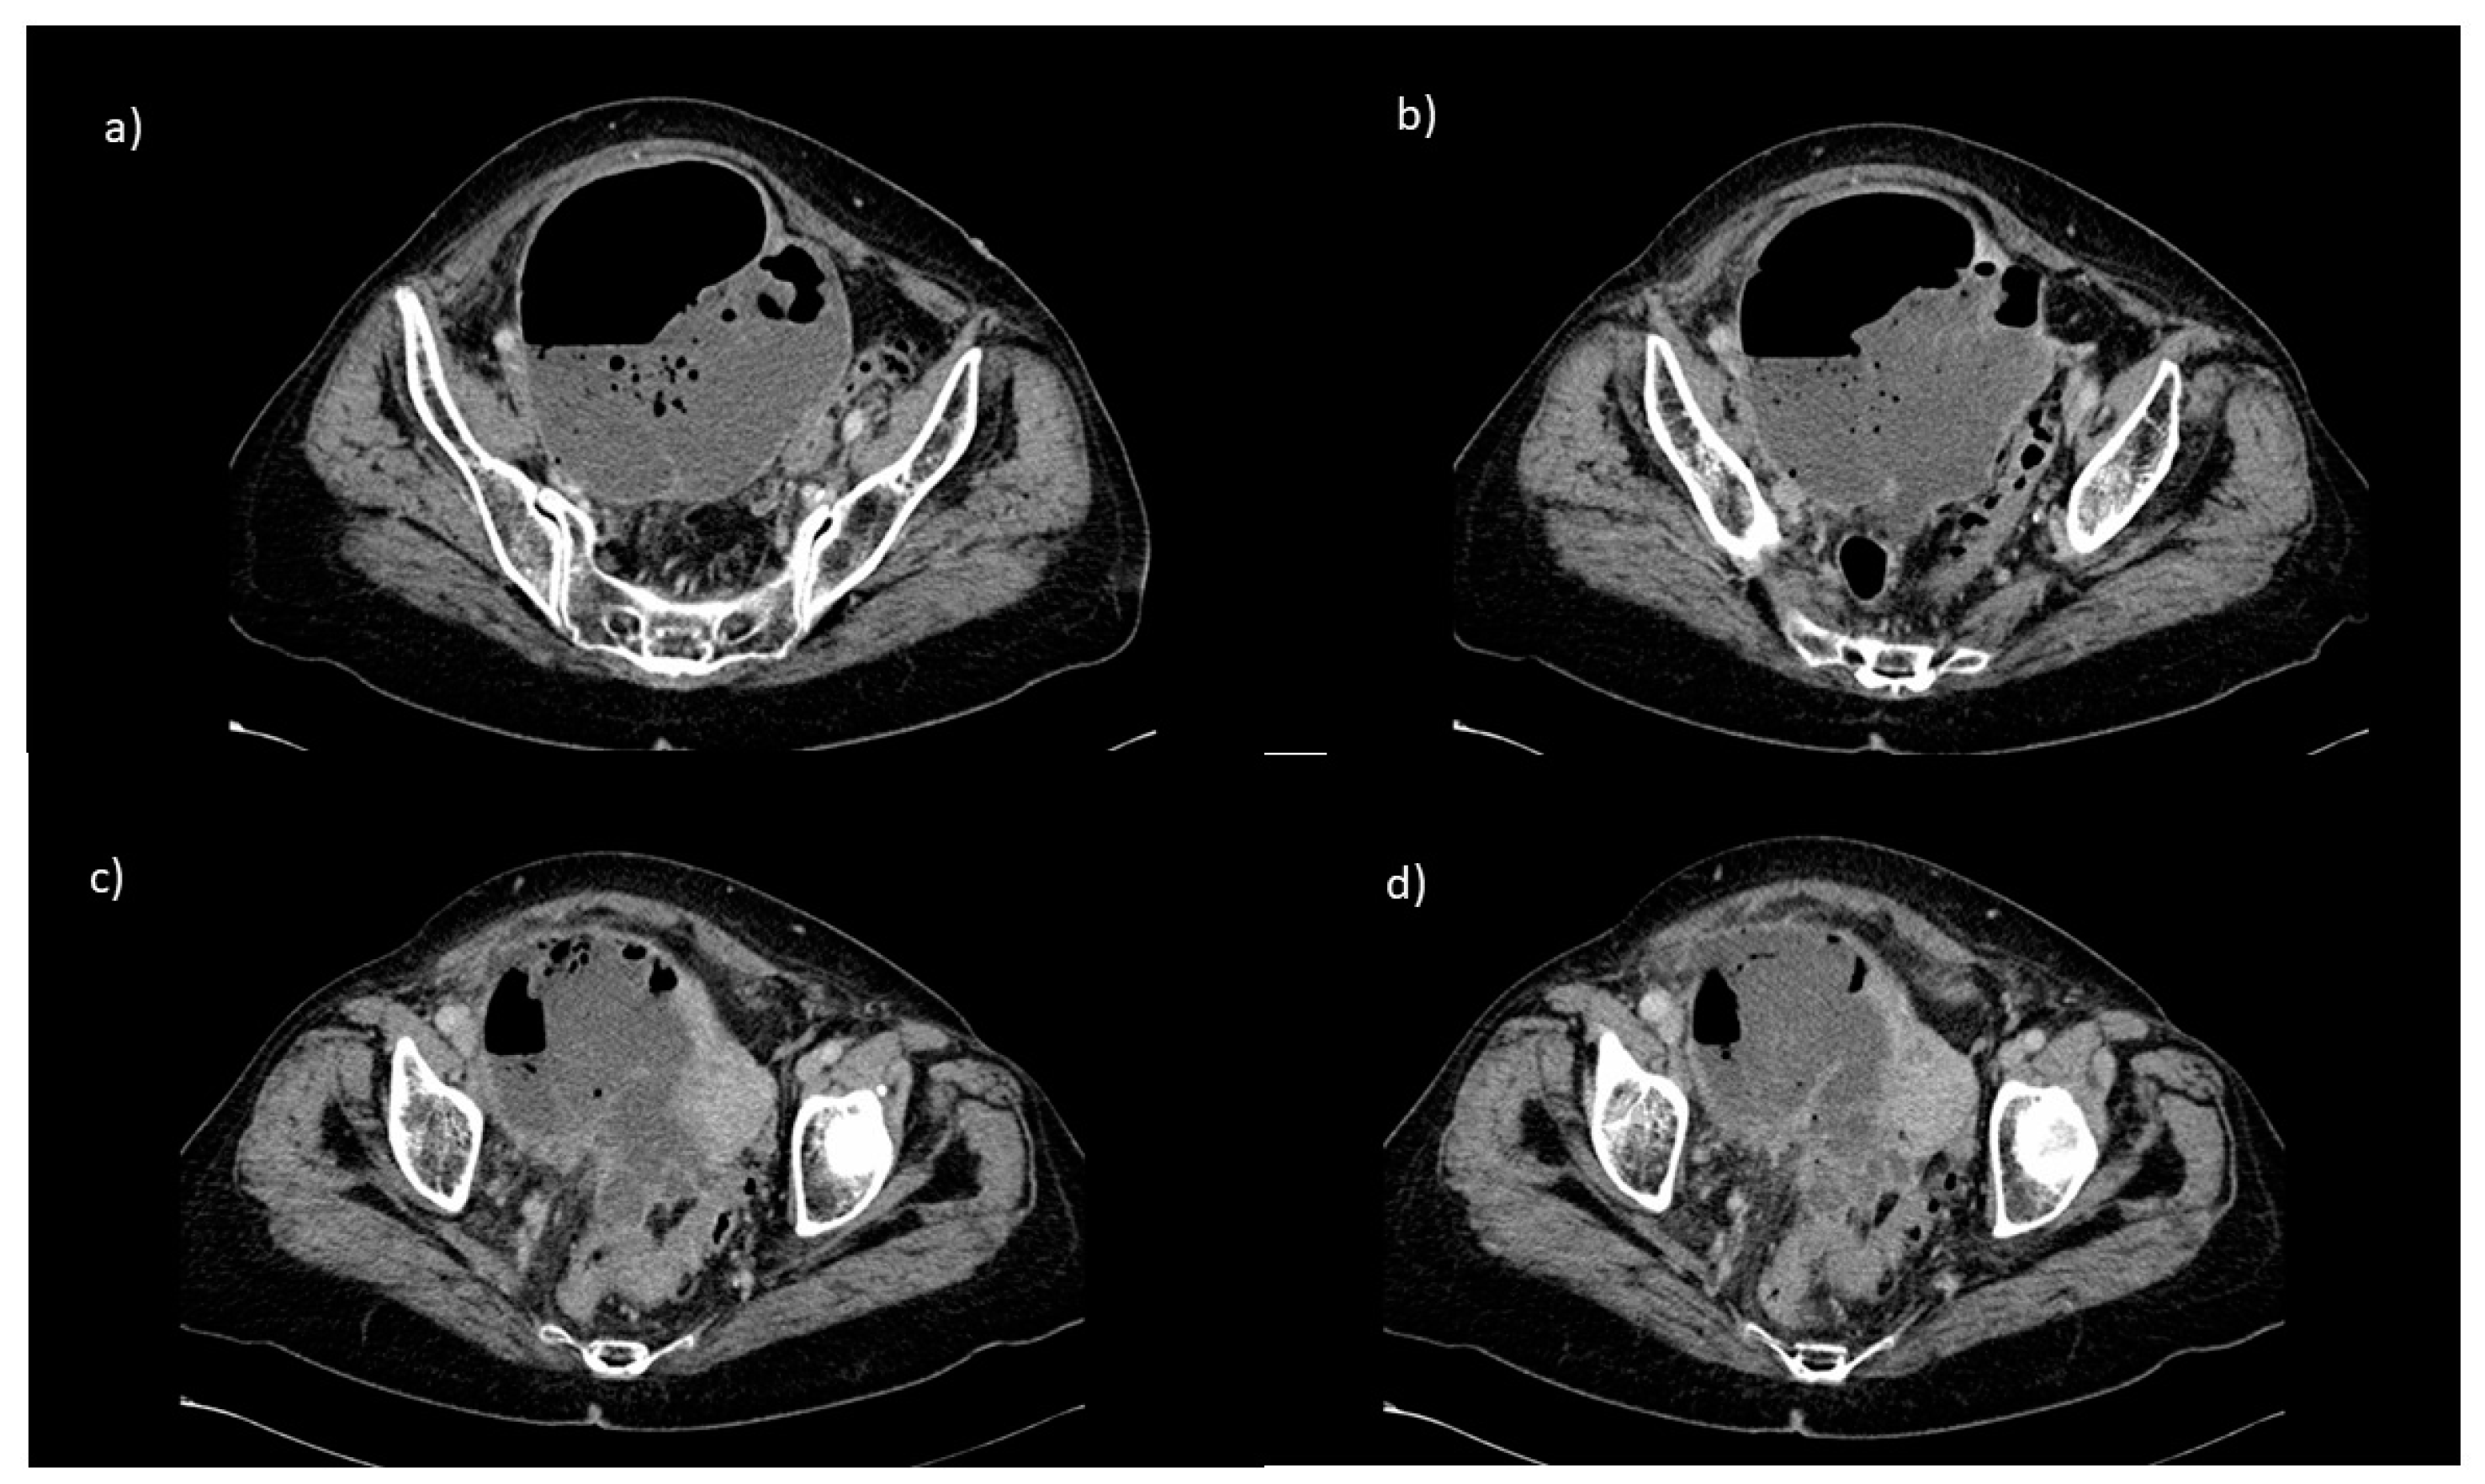

2. Case Report